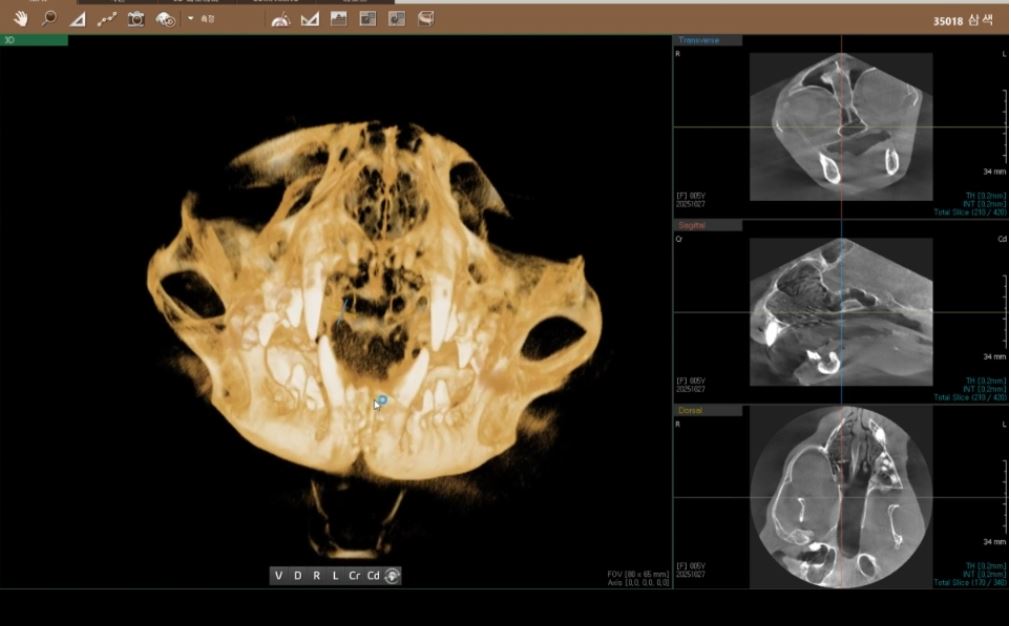

| 치료과정 | 선생님께서 삼색이 입안 사진을 보여주셨는데 밖에서 보여지는 것, 생각했던 것보다 심해 보였습니다. 피가 고여있고 점막궤양화가 진행되고 있다고 설명해주셨습니다. 치료 후 방사예정이라 송곳니라도 남기고 싶었지만 선생님께서 전발치를 권하셨고, 선생님 뜻에 따라 윗 앞니만 제외하고 전발치를 했습니다. 힘든 수술이었지만 아이가 잘 견뎌준것 같습니다. 3일 입원하며 통증 조절 시키고, 나머지 보름동안은 저희 집 케어장에서 케어하며 처방받은 스테로이드제와 항생제를 먹였습니다. 혀가 들어가고, 입 주변이 깨끗해지고, 그루밍을 할 수 있게되더니 털 상태까지 좋아지는 모습을 볼 수 있었습니다. 밥도 잘 먹어주어 너무 다행이었습니다. 원래도 말랐던 아이라 치료 기간 동안 많이 먹고 회복할 수 있도록 습식을 충분히 주었고, 방사 전에는 건사료도 잘 먹는 모습을 확인했습니다. 미모도 다시 되살아났습니다. |

선생님께서 삼색이의 입 안을 촬영해 보여주셨을 때, 겉에서 보던 모습과는 비교할 수 없을 만큼 상태가 심각해 보였습니다. 피가 고여 있었고, 점막이 궤양으로 진행되고 있다고 설명해주셨습니다. 치료 후 방사 촬영을 예정하고 있어 최소한 송곳니라도 남기고 싶었지만, 선생님께서는 전발치를 권하셨고 아이에게 가장 좋은 방향이라는 판단 아래 윗 앞니만 남기고 전발치를 진행했습니다. 긴 수술이었음에도 삼색이가 끝까지 잘 버텨준 것이 너무 대견했습니다.수술 후 3일간 입원하며 집중적으로 통증 조절을 받았고, 이후 보름 동안은 저희 집 케어장에서 처방받은 스테로이드제와 항생제를 복용하며 회복을 이어갔습니다. 시간이 지나면서 혀가 다시 잘 들어가고, 입 주변의 염증이 눈에 띄게 가라앉기 시작했습니다. 그루밍도 가능해지면서 털 상태까지 점점 좋아지는 모습을 보며 안심할 수 있었습니다. 무엇보다 밥을 잘 먹어주는 것이 큰 힘이 되었습니다. 원래 마른 체질이라 영양을 잘 채워줘야 한다는 마음으로 치료 기간 동안 습식 사료를 충분히 제공했고, 방사 전에는 건식 사료도 문제없이 먹는 모습을 확인했습니다. 그렇게 회복이 진행되면서 삼색이의 예쁜 모습과 생기까지 다시 살아나는 것을 보며 정말 다행이라고 느꼈습니다.

치아 엑스레이 발치 전, 후 사진입니다.